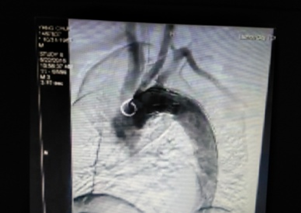

近日,我院成功開(kāi)展了一例主動(dòng)脈夾層腔內(nèi)修復(fù)術(shù)。此項(xiàng)技術(shù)的開(kāi)展為大動(dòng)脈疾病患者帶來(lái)福音,也標(biāo)志著我院在血管疾病介入治療方面提升到新的水平。?危險(xiǎn):兇猛“血管殺手”嚴(yán)重威脅健康60多歲的李大爺(化名),結(jié)腸腫瘤入院,完善相關(guān)檢查后確診為主動(dòng)脈夾層。主動(dòng)脈夾層是災(zāi)難性的血管疾病,堪稱“血管殺手”,如不及時(shí)...